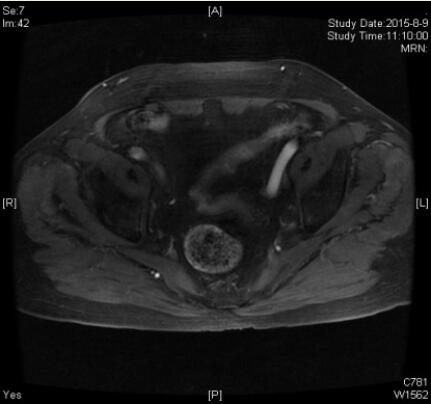

患者内分泌治疗半年后复查盆腔增强MRI,典型图片如下:

刘晓航教授:内分泌治疗后,可见前列腺体积缩小,前列腺内的占位目前已不明显,也未见明显的异常强化。两侧髂血管旁的肿瘤淋巴结也较前显著缩小,目前大小已处于正常范围,整体治疗效果是非常好的,因此此时病灶已经局限。